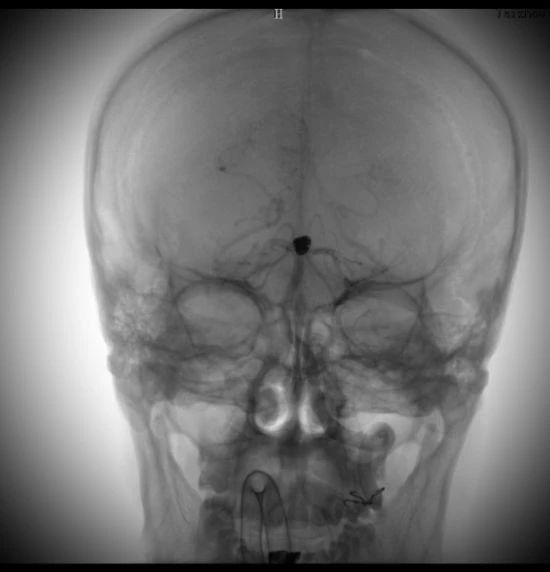

術(shù)后造影顯示,動脈瘤被致密栓塞

術(shù)后的動脈瘤長這樣。因為動脈瘤里填充了彈簧圈,所以在X線照射下整體看起來是黑色的

術(shù)后彈簧圈和顱內(nèi)支架的影像重建。圓球形的是彈簧圈,麻花樣的就是顱內(nèi)支架。